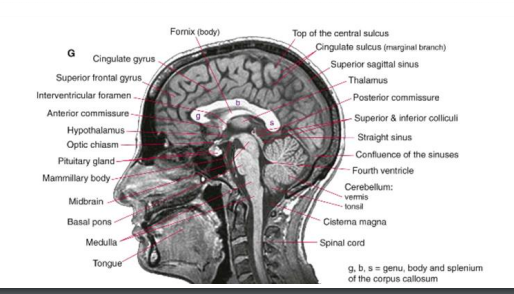

Much higher detail

Good for brainstem or cerebellare lesion